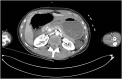

Presentation of case: Our patient is a 35-year-old female who was a restrained front seat passenger in a car vs. tree collision at 80 km/h. Her seat belt was worn with the shoulder strap under her left axilla. She sustained multiple injuries including complete transection of the gastroduodenal junction. In addition to this she had splenic, liver, transverse colonic, left lower rib and humeral injury. She underwent damage control laparotomy with splenectomy; re-look with gastrojejunostomy and transverse colonic resection with defunctioning ileostomy. She made a good recovery and was discharged after a 4 week admission.